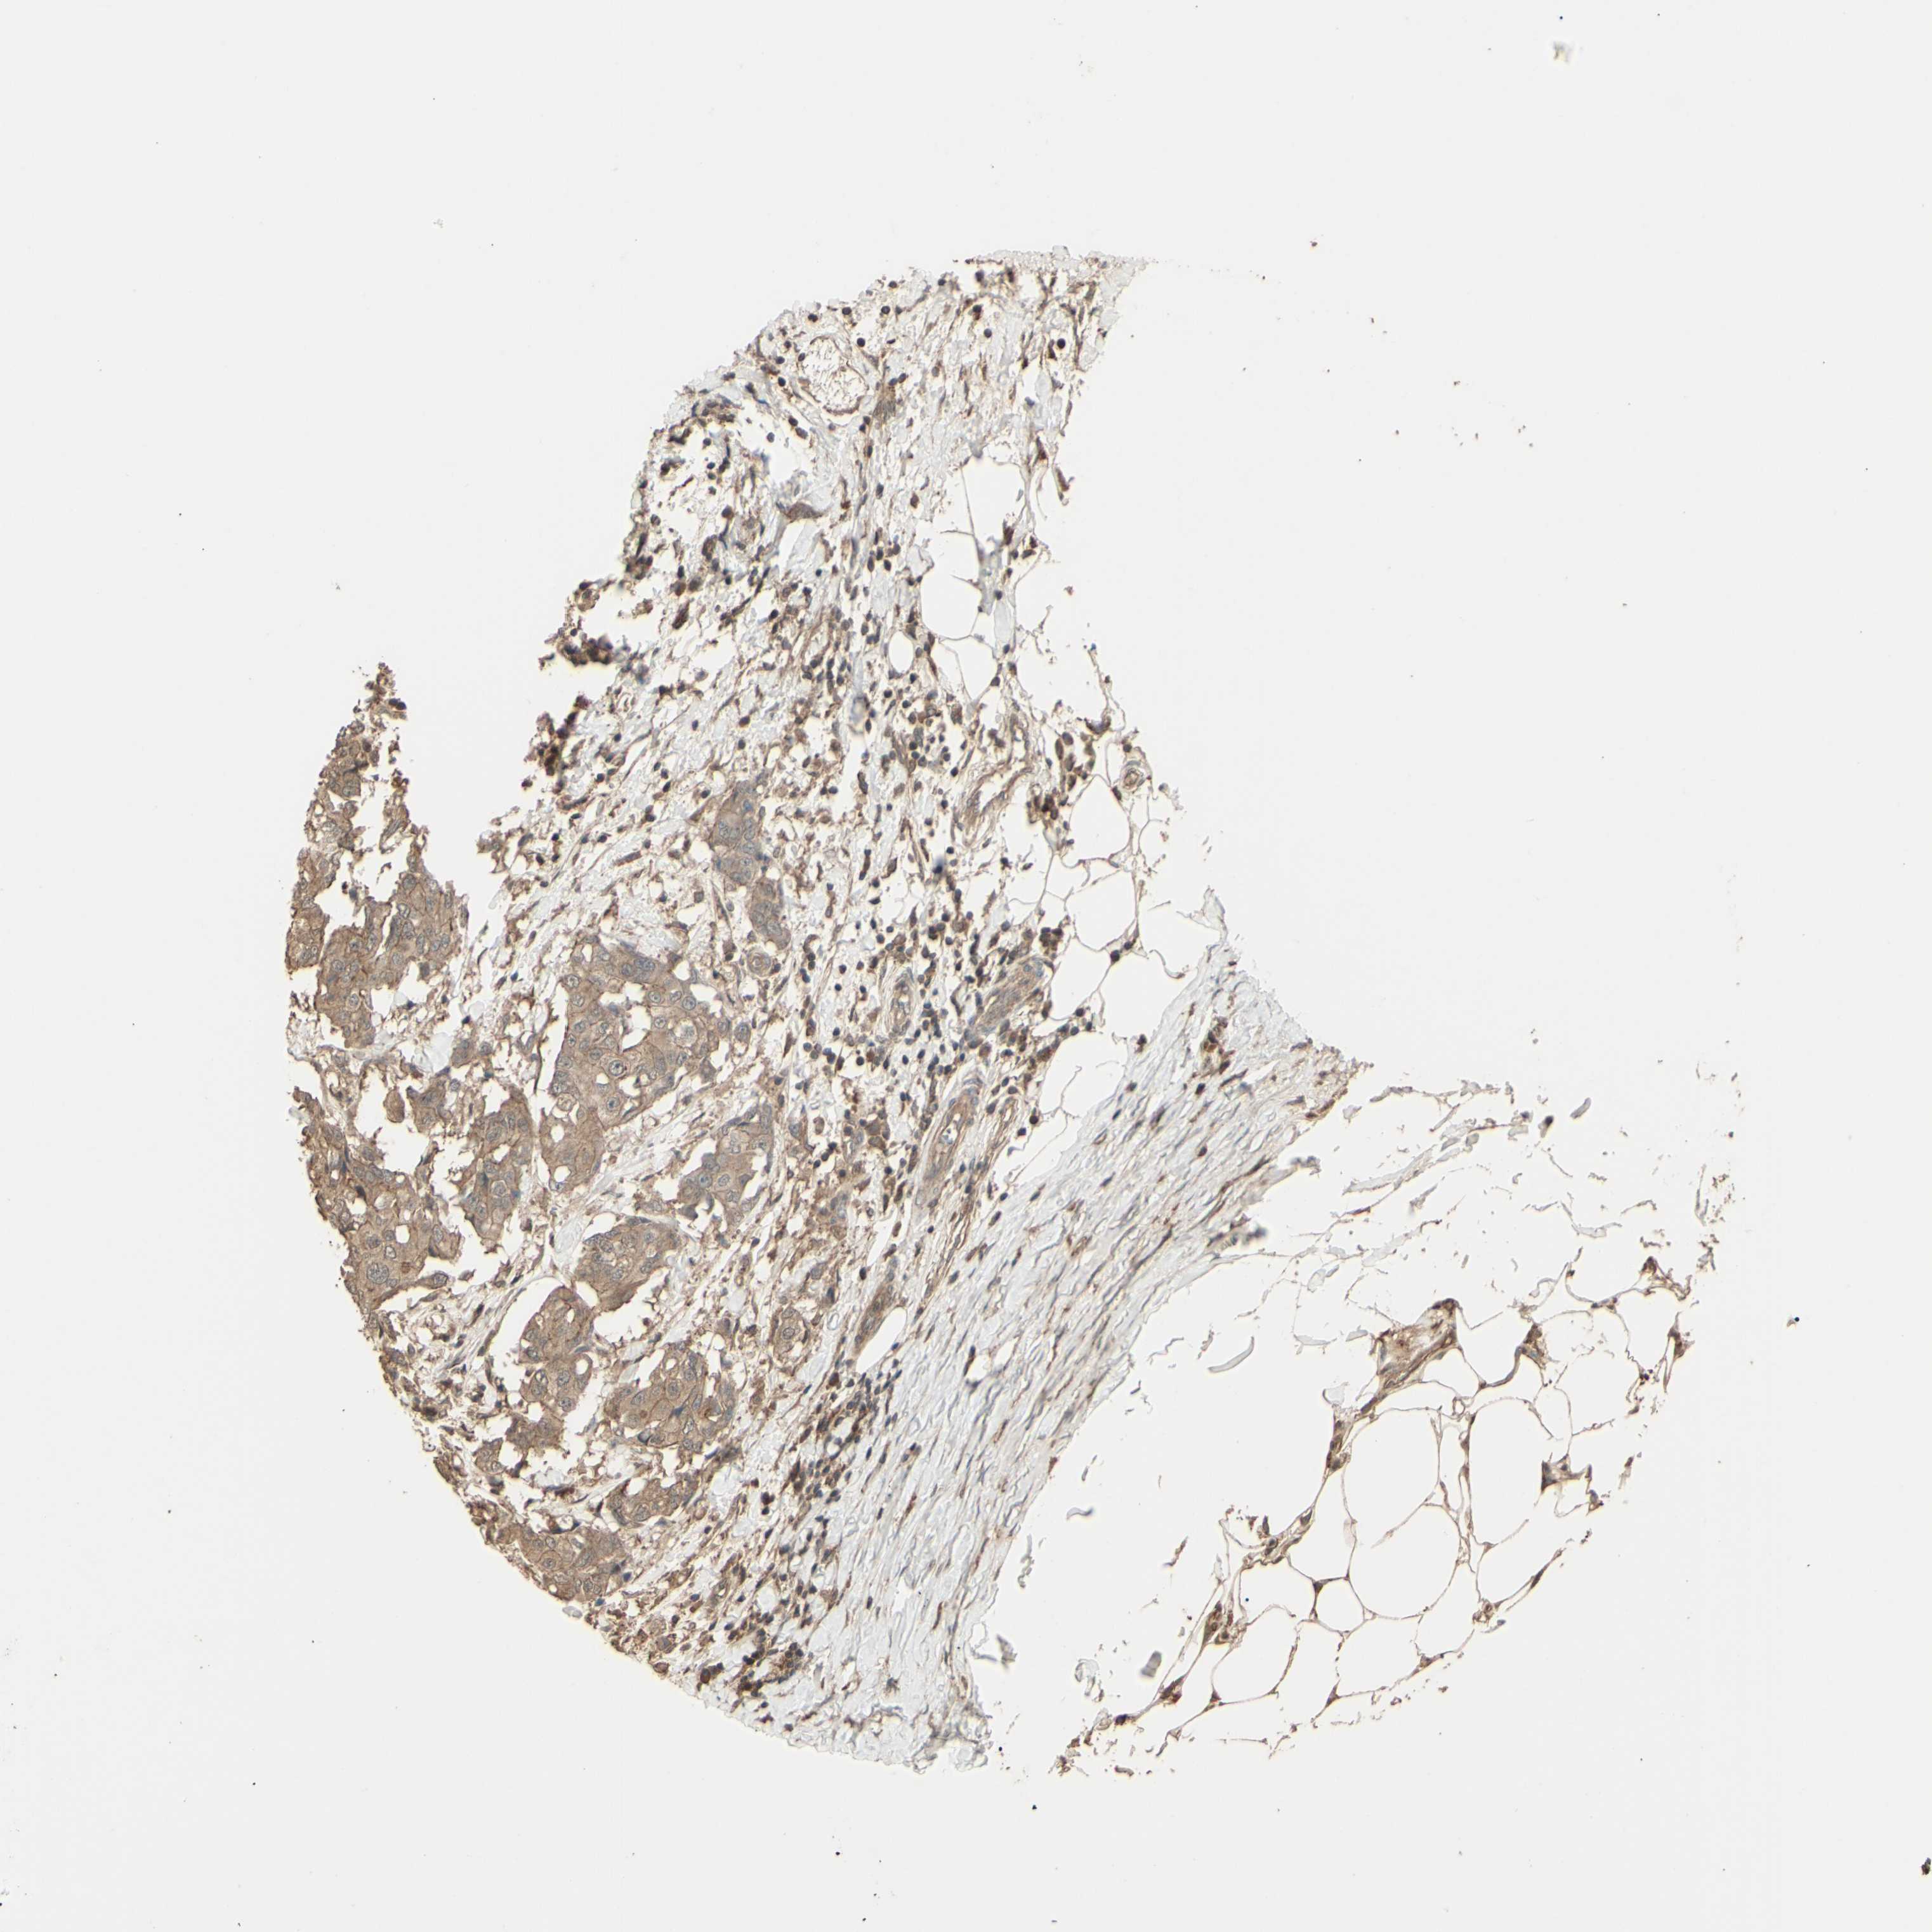

BRCA TCGA BRCA VALIDATION PROTEIN EXPRESSION

ANTIBODIES

AND

VALIDATION